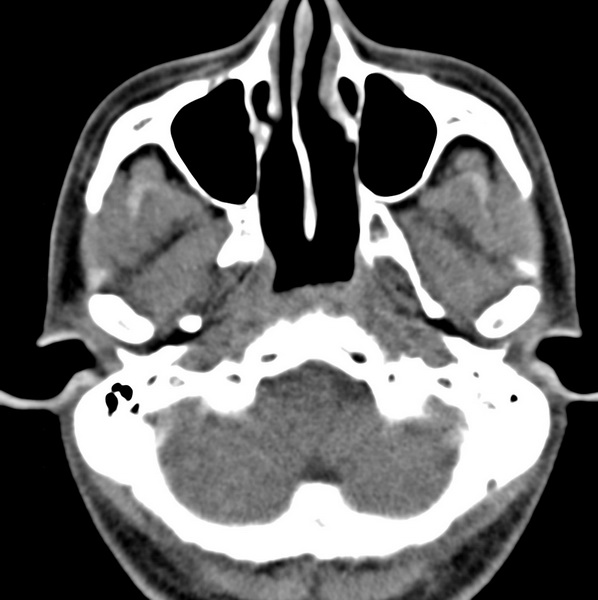

男、31、鼻咽部肿瘤放疗后请帮忙看看。

效果好,右侧破裂孔扩大,局部骨质缺损,为颅底骨质破坏。

1)鼻咽部肿瘤侵犯颅底放疗术后改变。2)左侧蝶窦炎。

咽后壁增厚,左侧咽鼓管隆突增大、咽鼓管咽口变浅,同侧咽旁间隙较窄。右侧颅底骨质破坏?为什么不在同一侧?

鼻咽部肿瘤侵犯颅底放疗术后改变.